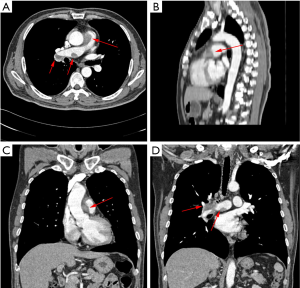

A 53-year-old man presented with exertional dyspnea and chest pain over 6 months, and suddenly developed hemoptysis 10 days ago. Contrast-enhanced computed tomography (CT) showed three filling defects in the main pulmonary artery, right pulmonary artery trunk and branch (Figure 1). Significant enhancement can be seen in the filling defects which grows along the vessel wall while the small vessel has no obvious embolism. Echocardiography performed that the main and right pulmonary artery had three hypoechogenic areas, and the blood flow in pulmonary artery was obviously accelerated. There was no risk factor for embolism in patient, and no abnormality in d-dimer and lower extremity vascular ultrasonography. Pulmonary artery computed tomography angiography (CTA) showed chronic thrombosis in the main pulmonary artery, right pulmonary artery, and branch. The lesions are large and may involve lung tissue. The lesion faces the blood flow surface full, bulging, unlike the pulmonary embolism is always a cup-shape. The result of positron emission tomography-computed tomography (PET-CT) is positive. It is performed that the size of the main pulmonary artery lesion was about 26 mm × 23 mm, the standardized uptake value maximum (SUVmax) value was 23.7, the lesion of the right pulmonary artery was about 14 mm × 20 mm, the SUVmax value was 11.3, the lesion size of the right pulmonary artery branch was about 16 mm × 20 mm, and the SUVmax value was 6.4 (Figure 2). PET is associated with abnormal increase in local glucose metabolism, therefore is considered as a primary malignant tumor of the pulmonary artery. The final clinical diagnosis of this patient is pulmonary artery sarcoma which is a rare neoplasm that appears always similar to pulmonary thromboembolism.

Pulmonary artery sarcoma is often misdiagnosed as pulmonary thromboembolism before operation or autopsy because of the lack of specificity of its clinical symptoms. In the acute phase of pulmonary thromboembolism, d-dimer is always increased. In the chronic phase, the results of CTA may indicate the reduction of vessel lumen which can be seen partial enhancement can be seen, and glucose metabolism may be increased. However, the SUVmax of lesion can’t reach as high as 23.9.